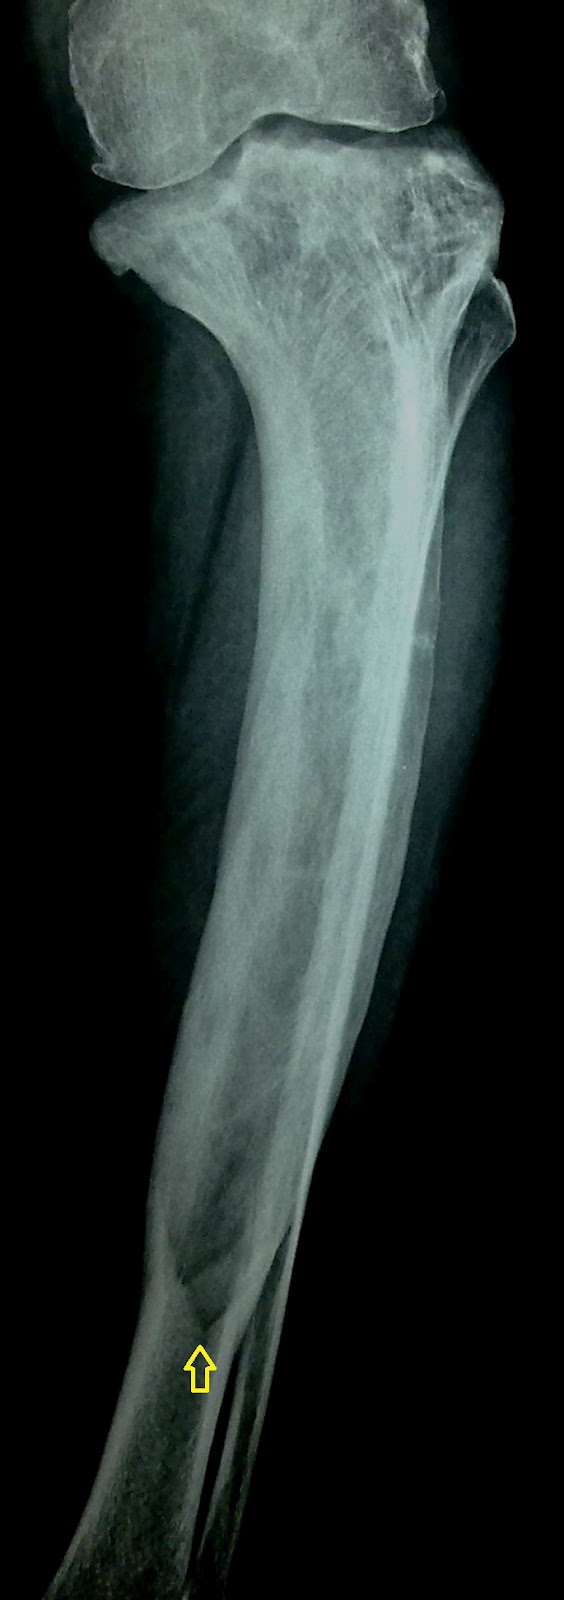

Lytic Phase Of Paget Disease Blade Of Grass Appearance Of The Download Scientific Diagram

Jefferson Radiology On Twitter Candle Flame Sign Also Blade Of Grass Sign Is Characteristic Of The Lytic Phase Of Paget S Disease Describes The Radiolucent Leading Edge Of A Long Bone Lesion